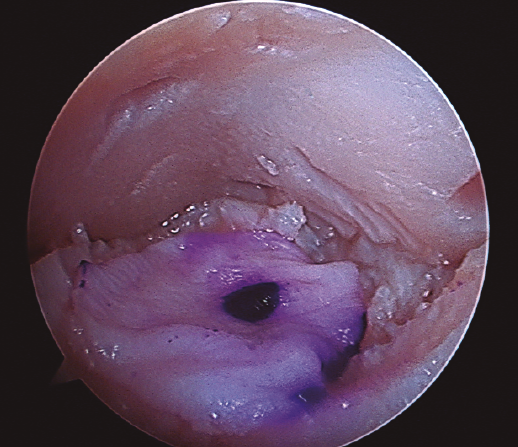

Figura 4. Aspecto final de la membrana de colágeno tapizando completamente el lecho de la lesión.

- Finalmente, procedemos a la colocación de la membrana previa fijación con Tissucol Duo® (sistema adhesivo de fibrina de 2 componentes congelado, tratado por vapor) (Figura 4) y esperaremos 10 minutos hasta comenzar la movilidad del tobillo y comprobar su estabilidad y la ausencia de pinzamiento de la misma.